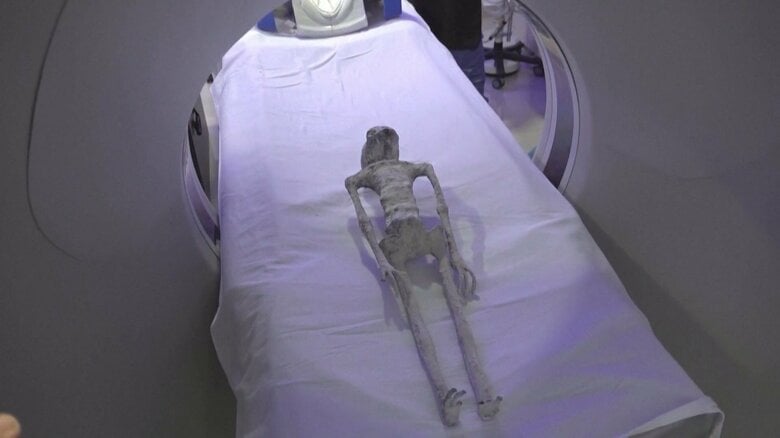

メキシコで、人間ではないとされるミイラ化した死体について、X線などによる検査が実施された。

手足は細長く、指は3本。

この物体は2017年、ペルーのナスカ地上絵の近くで発見され、先週、メキシコ議会で公開された。

こうした中メキシコの研究所は18日、この物体についてCTスキャンやX線検査を行った結果、「頭蓋骨の首はつながっていて組み立てられたり、人工的に操作された痕跡はない」と結論づけた。